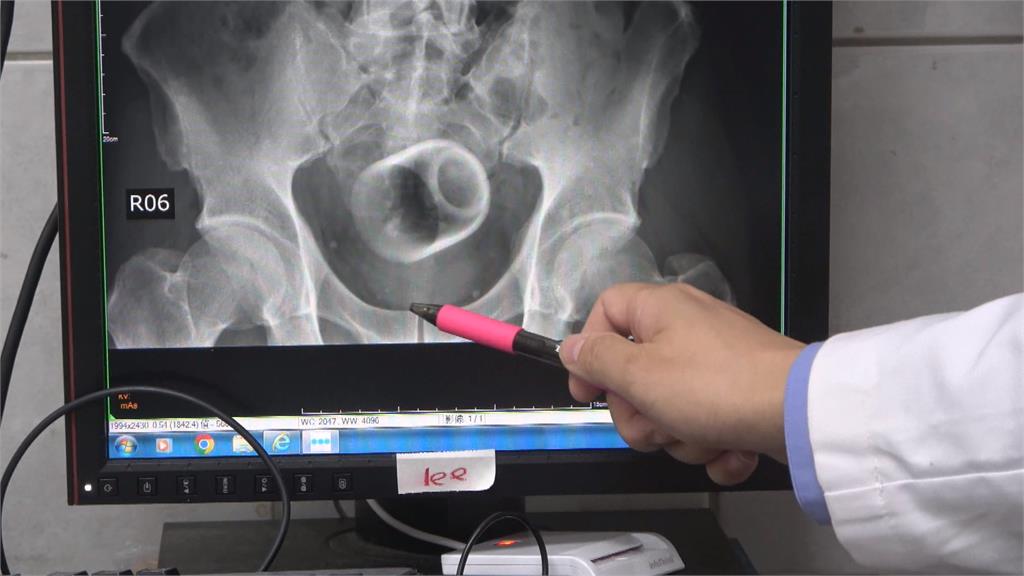

綠茶甘醇入喉,但拿來品茶的瓷杯,怎麼莫名其妙,出現在男子的骨盆腔內。X光攝影一照,杯子清晰可見,連看診的醫師,都感到十分詫異。

原來,台中市這名男子,腹脹超過三天無法解便,肚子痛到受不了,不得已到醫院求診,但他起先害羞不提及自己肛門塞了一個杯子,最後在X光檢查之下才被發現,不過由於杯緣光滑,無法使用器械取出,加上杯子全被大腸包住,部分腸子缺血造成壞死,最後只好全身麻醉,開腸破肚取出杯子。醫師表示,肛門塞進異物,臨床上是基於好奇或想要尋求刺激,提醒此舉可能造成肛門括約肌鬆弛失禁,甚至讓腸子壞死破裂,嚴重的話,會引發腹腔感染,併發腹膜炎,甚至有致死危機。